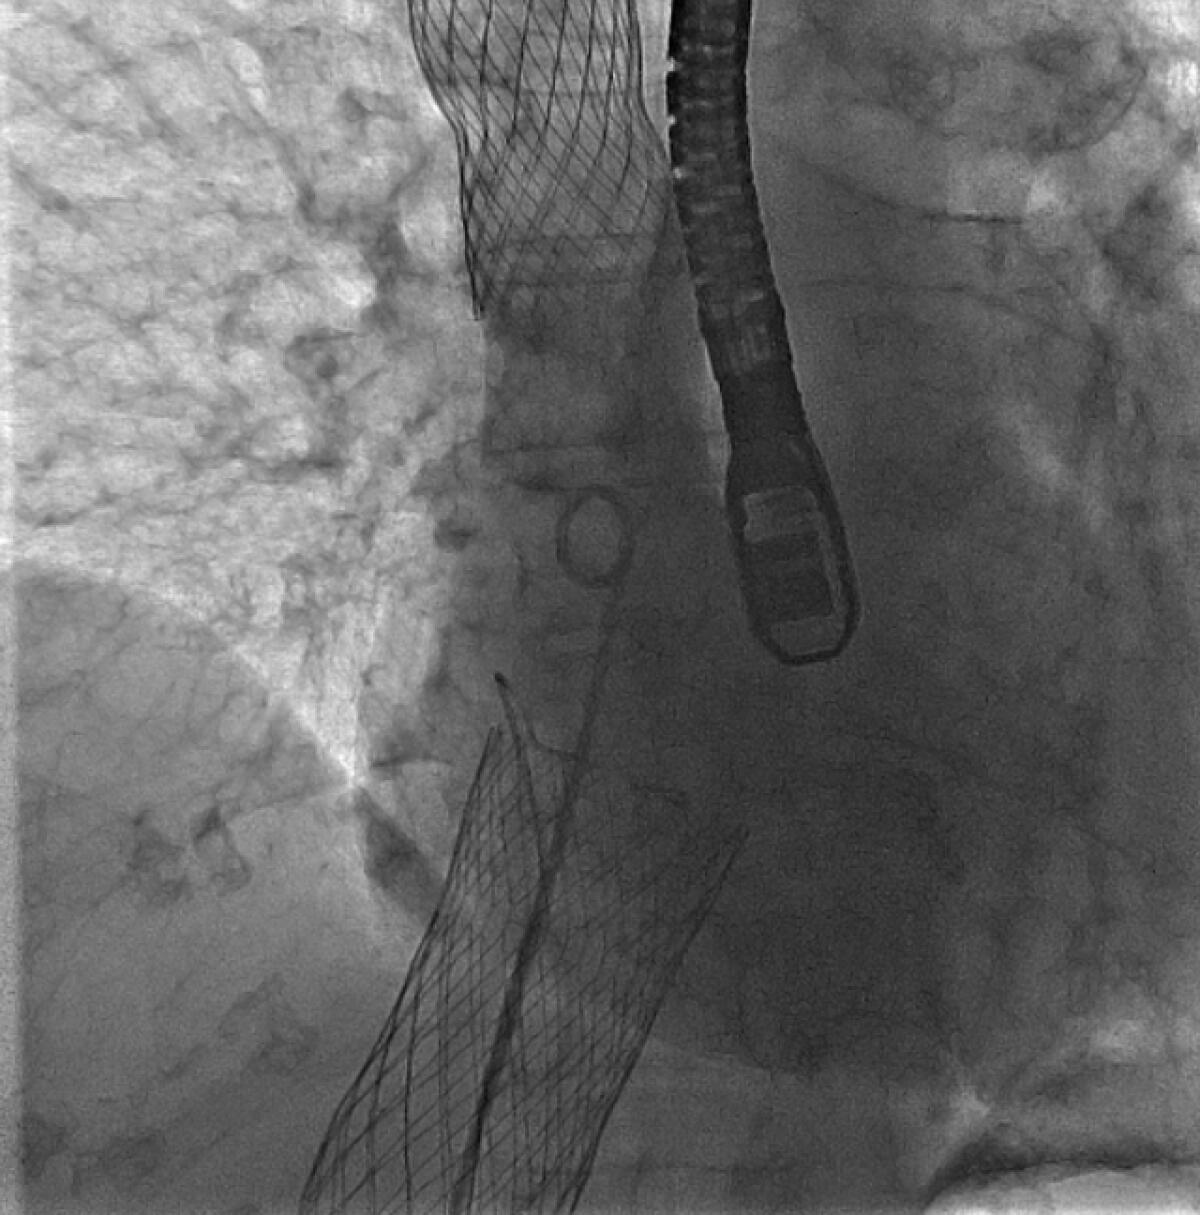

Un “impianto percutaneo di valvola tricuspide”  è stato eseguito per la prima volta a Benevento, tra le prime esperienze anche nel Sud Italia, un innovativo intervento presso l'UOC di Cardiologia dell’Ospedale Sacro Cuore di Gesù “Fatebenefratelli” del capoluogo sannita diretta dal prof. Bruno Villari. La paziente era affetta da una severa forma di insufficienza valvolare tricuspidale, molto sintomatica con diversi accessi in Ospedale negli ultimi mesi per scompenso cardiaco acuto. L’insufficienza valvolare tricuspidalica è una patologia comune nella popolazione anziana e frequentemente correlata a patologie del cuore sinistro o all’ipertensione polmonare.  Il trattamento con terapia medica è associato a scarsi risultati clinici purtroppo, e la chirurgia a torace aperto resta il gold standard per il trattamento, seppur gravata da una elevata mortalità e morbilità. Il caso della paziente trattata al “Fatebenefratelli di Benevento” è stato discusso in Heart Team e collegialmente si è deciso di procedere all’intervento percutaneo. Il sistema utilizzato (TricValve) prevede l'impianto di due protesi biologiche a livello delle vene cave (superiore e inferiore) per prevenire il reflusso di sangue e trattare la congestione venosa.  Le protesi vengono impiantate attraverso un catetere inserito nella vena femorale, evitando così un'operazione a cuore aperto.  L’intervento è stato effettuato nel Laboratorio di Emodinamica dall’equipe composta dai dottori Bruno Villari, Eugenio Laurenzano e Bruno Petruzziello, sotto guida transesofageo del dott. Quirino Ciampi per il corretto posizionamento.